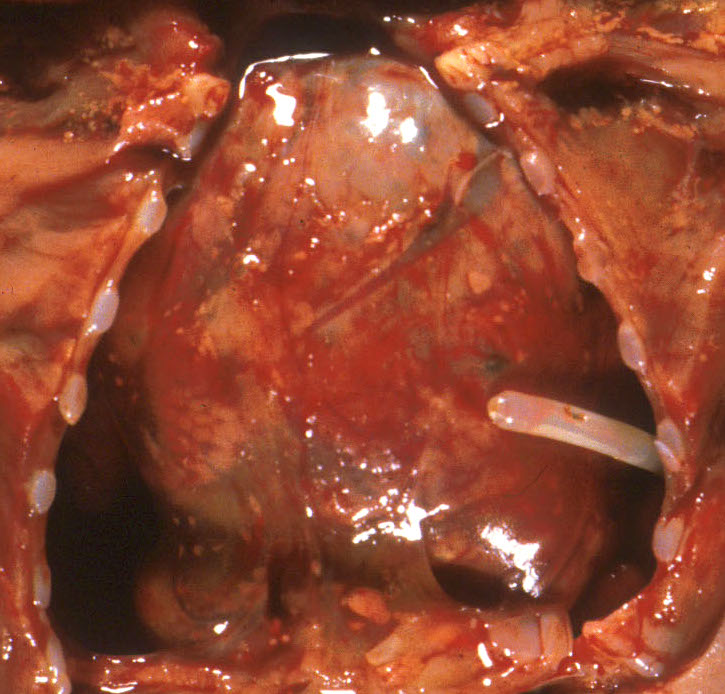

The other mechanism producing pulmonary hypoplasia is a mirror image of oligohydramnios in that external forces within the chest cause restricted lung growth by opposing the lung expansion from the amniotic fluid pressure. These forces may include an intrathoracic mass effect from tumor or fluid (Fig 3a, b)

, or restriction of the thoracic volume by an osteochondrodystrophy (Fig 4a, b).

A diaphragmatic hernia is another form of mass effect, but in addition may also have a primary abnormality of lung development on the side with the hernia. Even in the normal thorax, the smaller left, compared to right, lung may be smaller because of the predominance of the heart mass in the left side of the thoracic cavity. Fluid having a mass effect is usually from a pleural effusion from anasarca due to heart failure which is termed by tradition as fetal hydrops. The causes of fetal hydrops will be presented in the obstetrical pathology chapter on fetal anomalies associated with perinatal death. A less common cause of pleural effusion is an abnormality of lymphatic drainage either from thoracic lymphangiectasia and failure of normal thoracic duct formation. Lymphatic fluid has a higher protein content than that in an effusion. An abnormality of lymphatic drainage may be associated with a mediastinal shift from asymmetric fluid accumulation (Fig 5a, b).